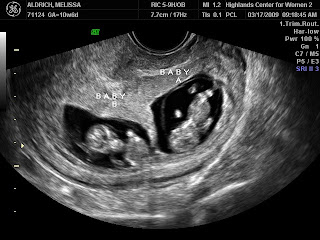

2009I had my second OB appointment last week and was just amazed to see how much the little ones had grown over the last month! They went from looking like little aliens:

to looking like sweet babies!

2009There’s a certain surreal quality to being told you’re having twins. Here you are barely 12 weeks pregnant and just adjusting to the idea that there’s a kiddo inside of you and BAM! you find out there’s two. Ofcourse, Derek had totally prepared me for the twin diagnosis so it didn’t catch me completely off guard. Actually, when I told Derek I was pregnant his first response was something along the lines of “Cool. You’re having twins.” He teased me about it every single day until the ultrasound. There we were viewing the first pictures of our little one and I get up the nerve to gloat. “Ha! I told you we weren’t having twins!” To which the sweet ultrasound technician says, “Well,… um… actually… I was about to show you the second baby. We like to warm you up to the idea first.” No more gloating from me. I kicked Derek square in the tush twice (once for each baby) on the way out of the OB office. And the poor boy has tolerated more sighs and pointed fingers in his direction with the only word possible from me being “Twins.”